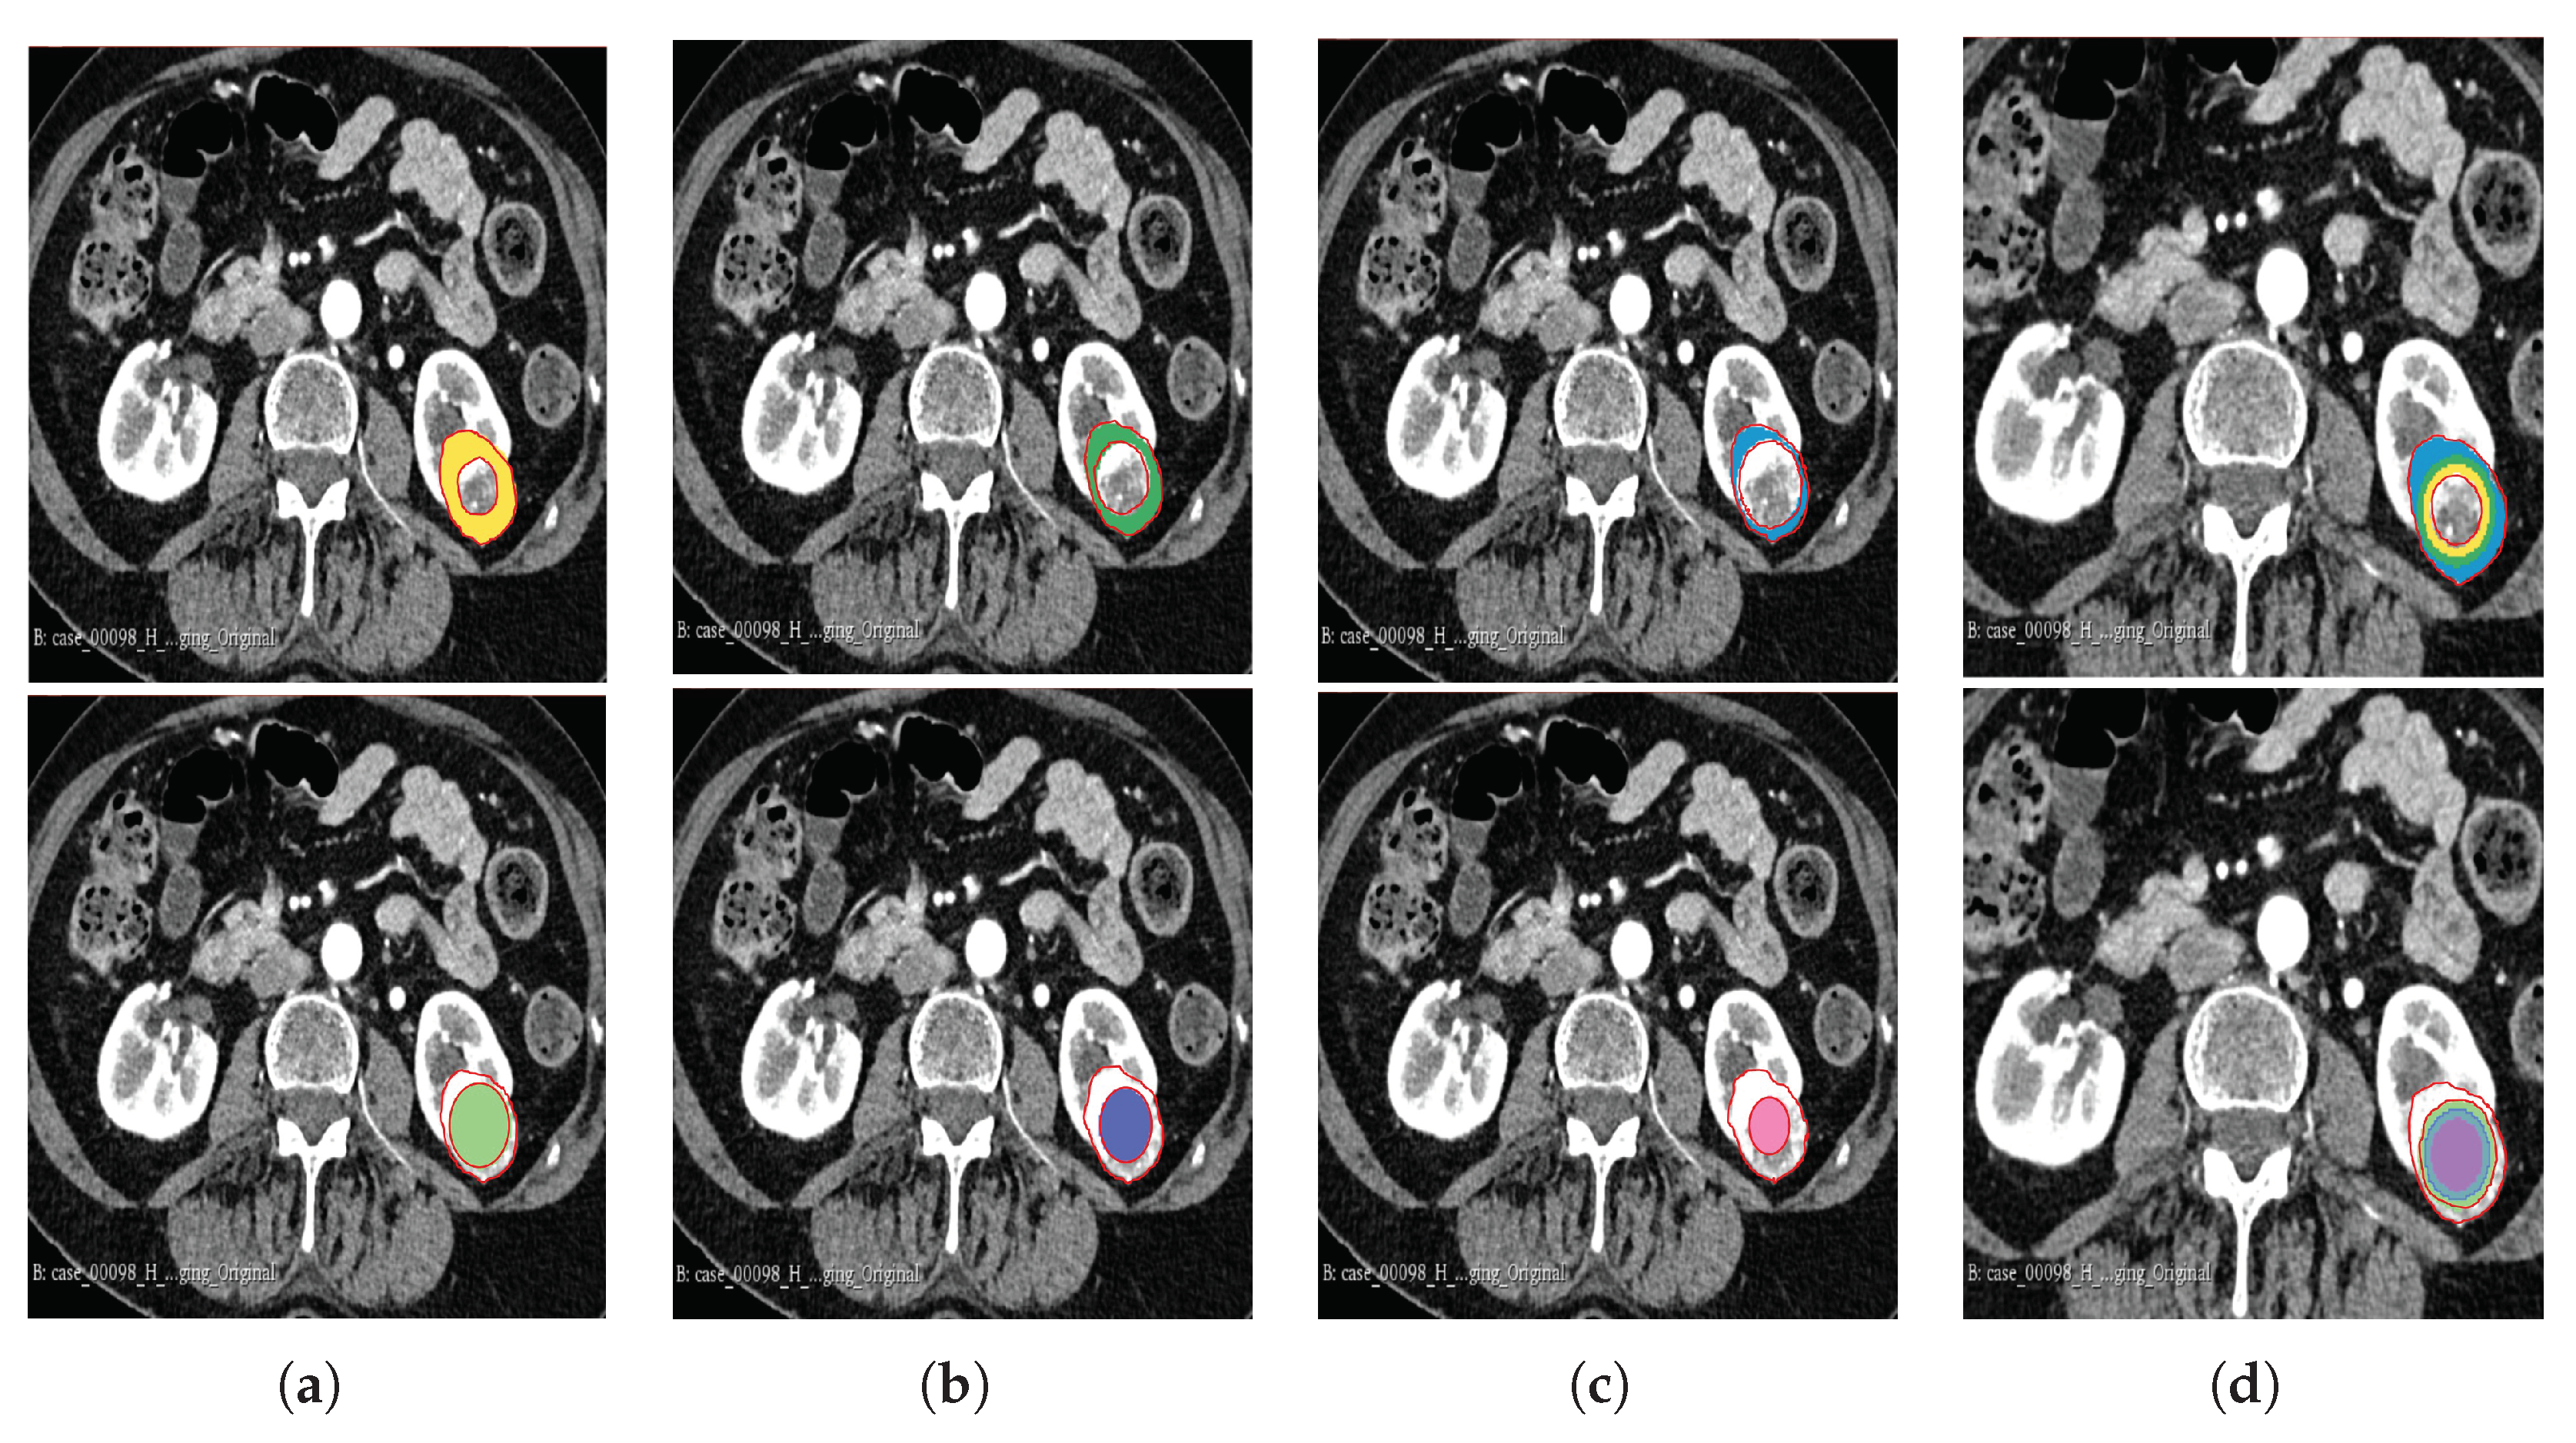

The segmentation result for both cohorts 1 and 2 was a binary mask of the tumour. In the present study, the tumours were divided into different sub-regions based on their geometry (i.e., periphery and core). The periphery refers to regions towards the edges of the tumour, whereas the core represents regions close to the centre of the tumour. The core was obtained by extracting 25%, 50%, and 75% of the binary mask from the centre of the tumour, while the periphery was generated `by extracting 25%, 50%, and 75% of the binary mask starting from the edges of the tumour to form a rim as a hollow sphere. A detailed visual description is shown in Figure 2, Figure 3, and Figure 4. Mask generation was performed using a Python script which automatically generated the sub-regions by image subtraction techniques.